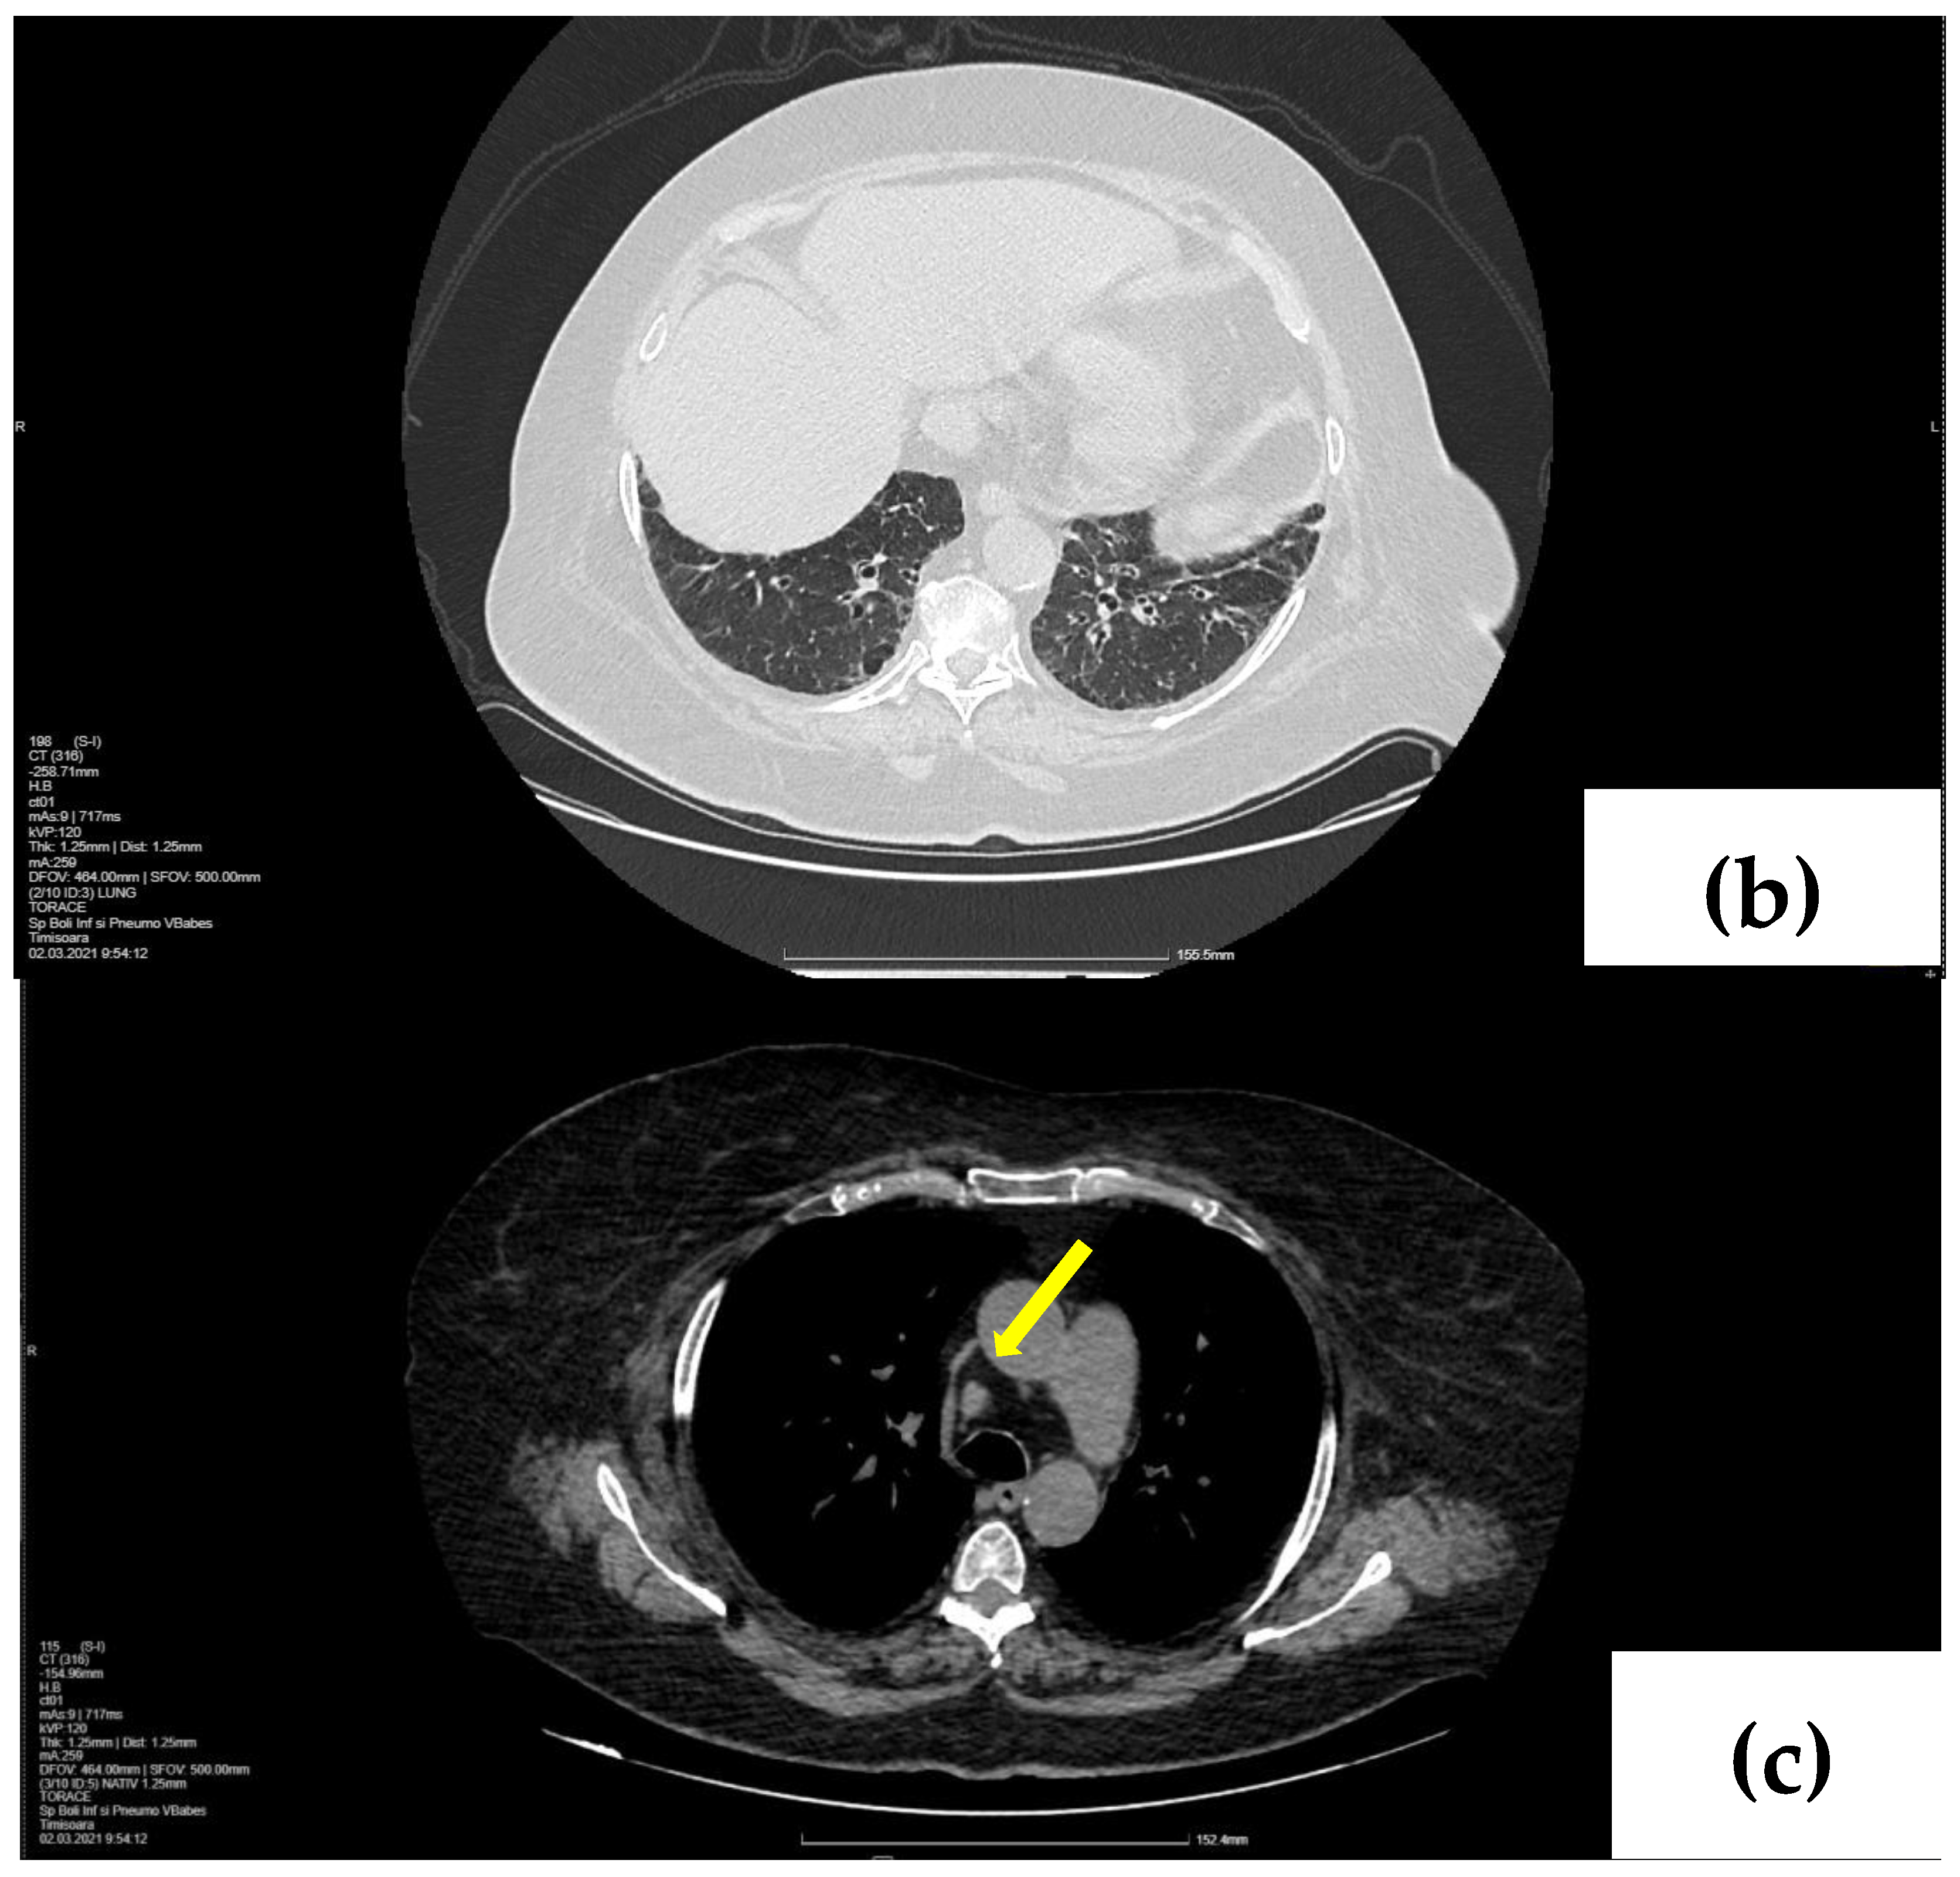

2.1. Laboratory, Radiological, and Histological Examinations

2.2. Treatment and Outcome